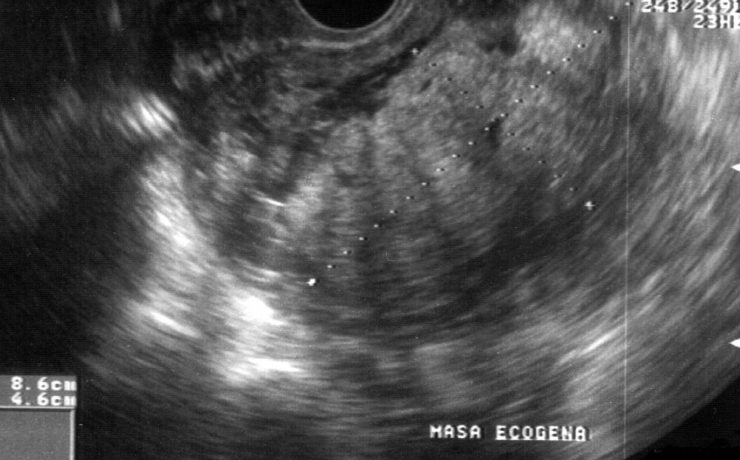

Rotura uterina por acretismo placentario

La rotura uterina durante el embarazo es una de las complicaciones más graves, que aumenta la morbilidad y mortalidad materna y fetal. La rotura uterina por placenta percreta es rara. La rotura uterina es cualquier desgarro, fracción o solución de continuidad supracervical en el útero que sucede durante el embarazo,